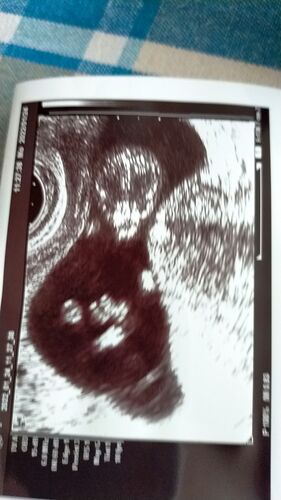

妊娠届とか、検査で宇宙を感じた事とか~

妊娠届、提出してきました。 アンケート項目が、回答に困るものが多かったけど、わりと正直に記入し、恐る恐る提出。 回答に困ったアンケートの内容はだいたいこんな感じ⇩ 妊娠届のアンケートの回答に困る - 鯖缶ランドリィ (hatenablog.com) 結局ですね、病…